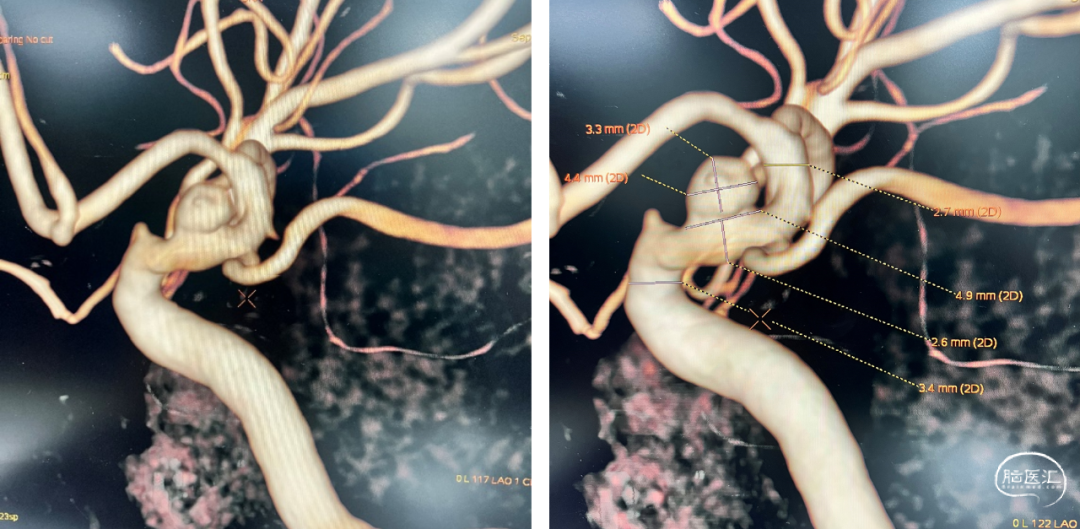

术前头颅CT及DSA检查显示:患者右侧颈内动脉眼段有一宽颈动脉瘤。

自发性蛛网膜下腔出血:右侧颈内动脉眼段血泡样动脉瘤破裂出血。

患者仰卧位,全麻成功后,常规腹股沟区消毒铺无菌巾,行右股动脉穿刺,置入6F 90cm动脉长鞘后送至颈内动脉C1段,行颈内动脉三维旋转造影。